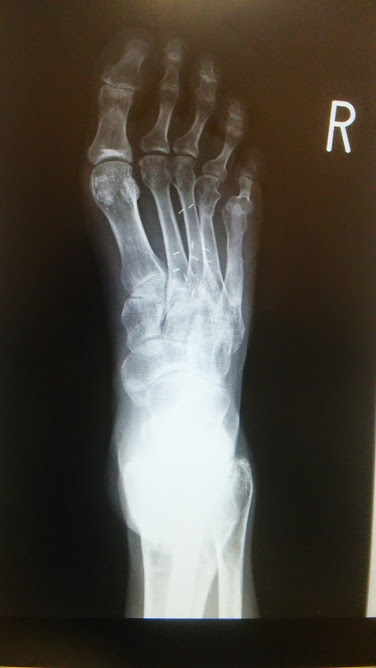

恒例の写真撮影をお願いしたら

前と同じように撮らせてもらいました

今悩みの種

甲の骨が反っているので

素足で歩くのが厳しい状態

今まで当たらなかった靴が当たる

小指と同じ現象に

小指の骨がガタガタです

何度かOPEしたせい

しばらく温存治療などしつつ経過観察